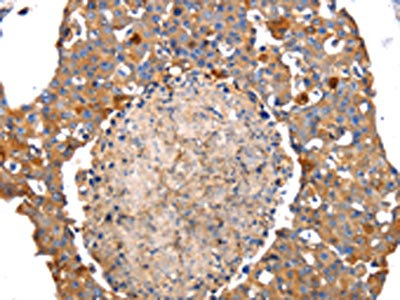

The image on the left is immunohistochemistry of paraffin-embedded Human breast cancer tissue using CSB-PA969280(IRS2 Antibody) at dilution 1/100, on the right is treated with synthetic peptide. (Original magnification: ×200)